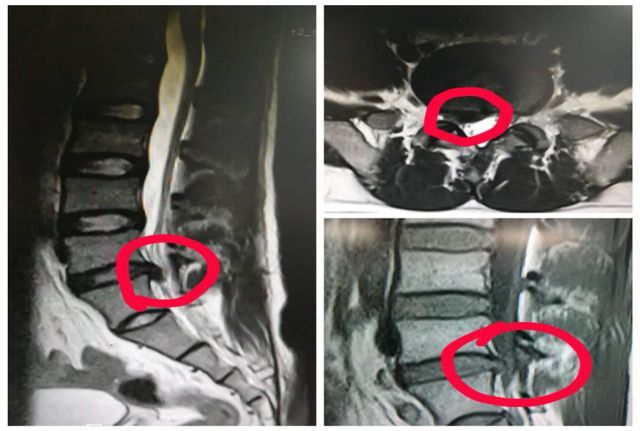

(该男子的影像学检查可见明显腰椎间盘突出)